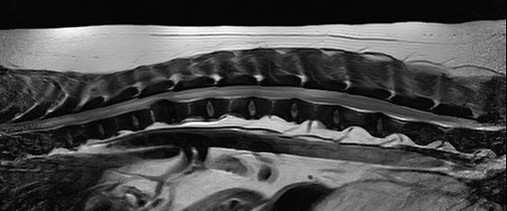

8才7ヶ月齢ミニチュアダックスフンド グレード5のT12-13椎間板ヘルニアです。病変部からT8までの脊髄はT2強調で高信号を呈しており、画像上、脊髄軟化症が強く疑われました。即日手術となり片側椎弓切除を実施したところ、硬膜には発赤が認められました。硬膜切開を実施したところ脊髄は軟化しており、後に病理組織検査で脊髄軟化症と診断されました